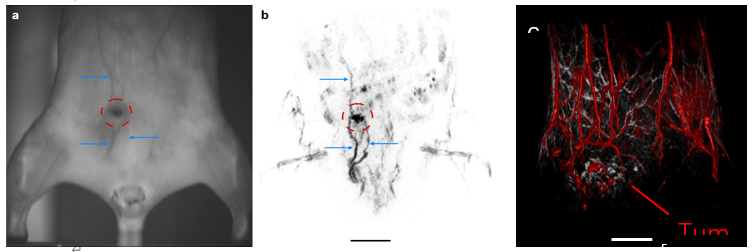

无毛小鼠(左)和 nu/nu 小鼠(右)中的人类乳腺癌异种移植(BT474 细胞)。(a、b)显示了相机观察结果和相应的冠状 MIP 板,由 700 nm 和 1064 nm 激光激发获得的 TriTom 图像构建而成。蓝色箭头和红色 ROI 表示高分辨率图像中可见的浅表血管特征和肿瘤环境。(c)复合皮肤(532 nm;灰色)和深层组织(890 nm;红色)3D 图像。肿瘤大小 = 10.6 x 4.7 x 11.6 mm3

转移性乳腺癌活体小鼠模型中的深层和浅表血管 TriTom 复合图像

红色 – 深层血管(890 nm 激发)

黄色 – 浅层血管(532 nm 激发)